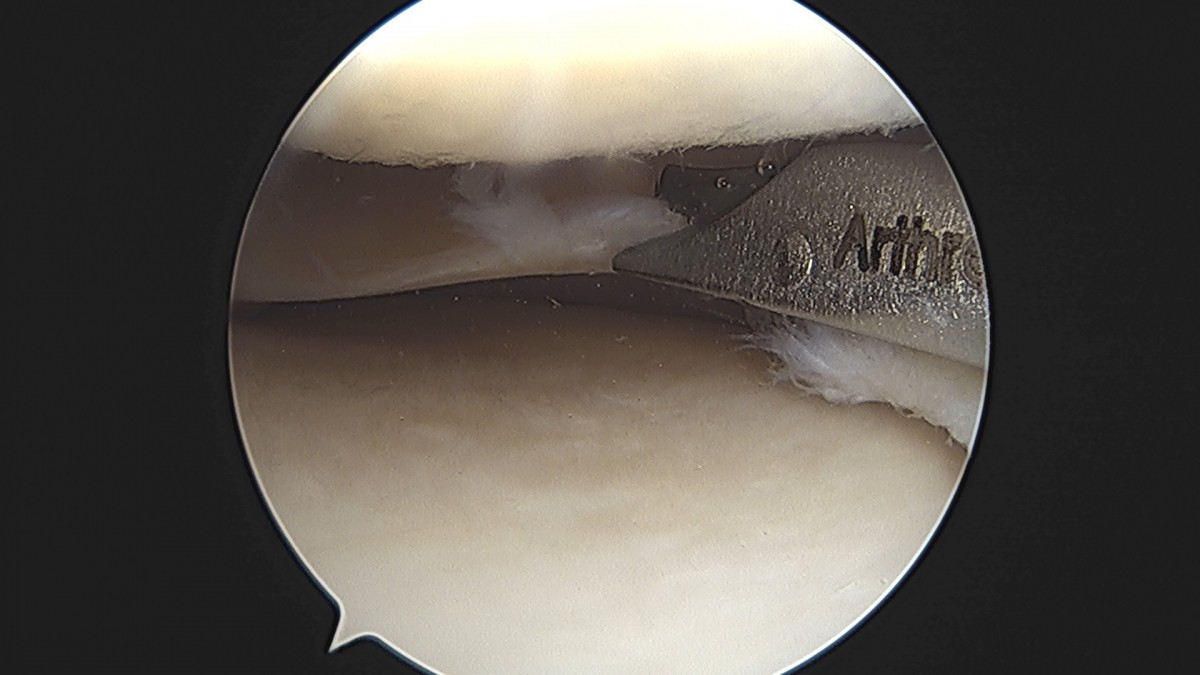

이재상원장님 무릎 반월상 연골판 절제술 박강O 환자

작성자 최고관리자 댓글 0건 조회 381회 작성일 25-09-16 15:47